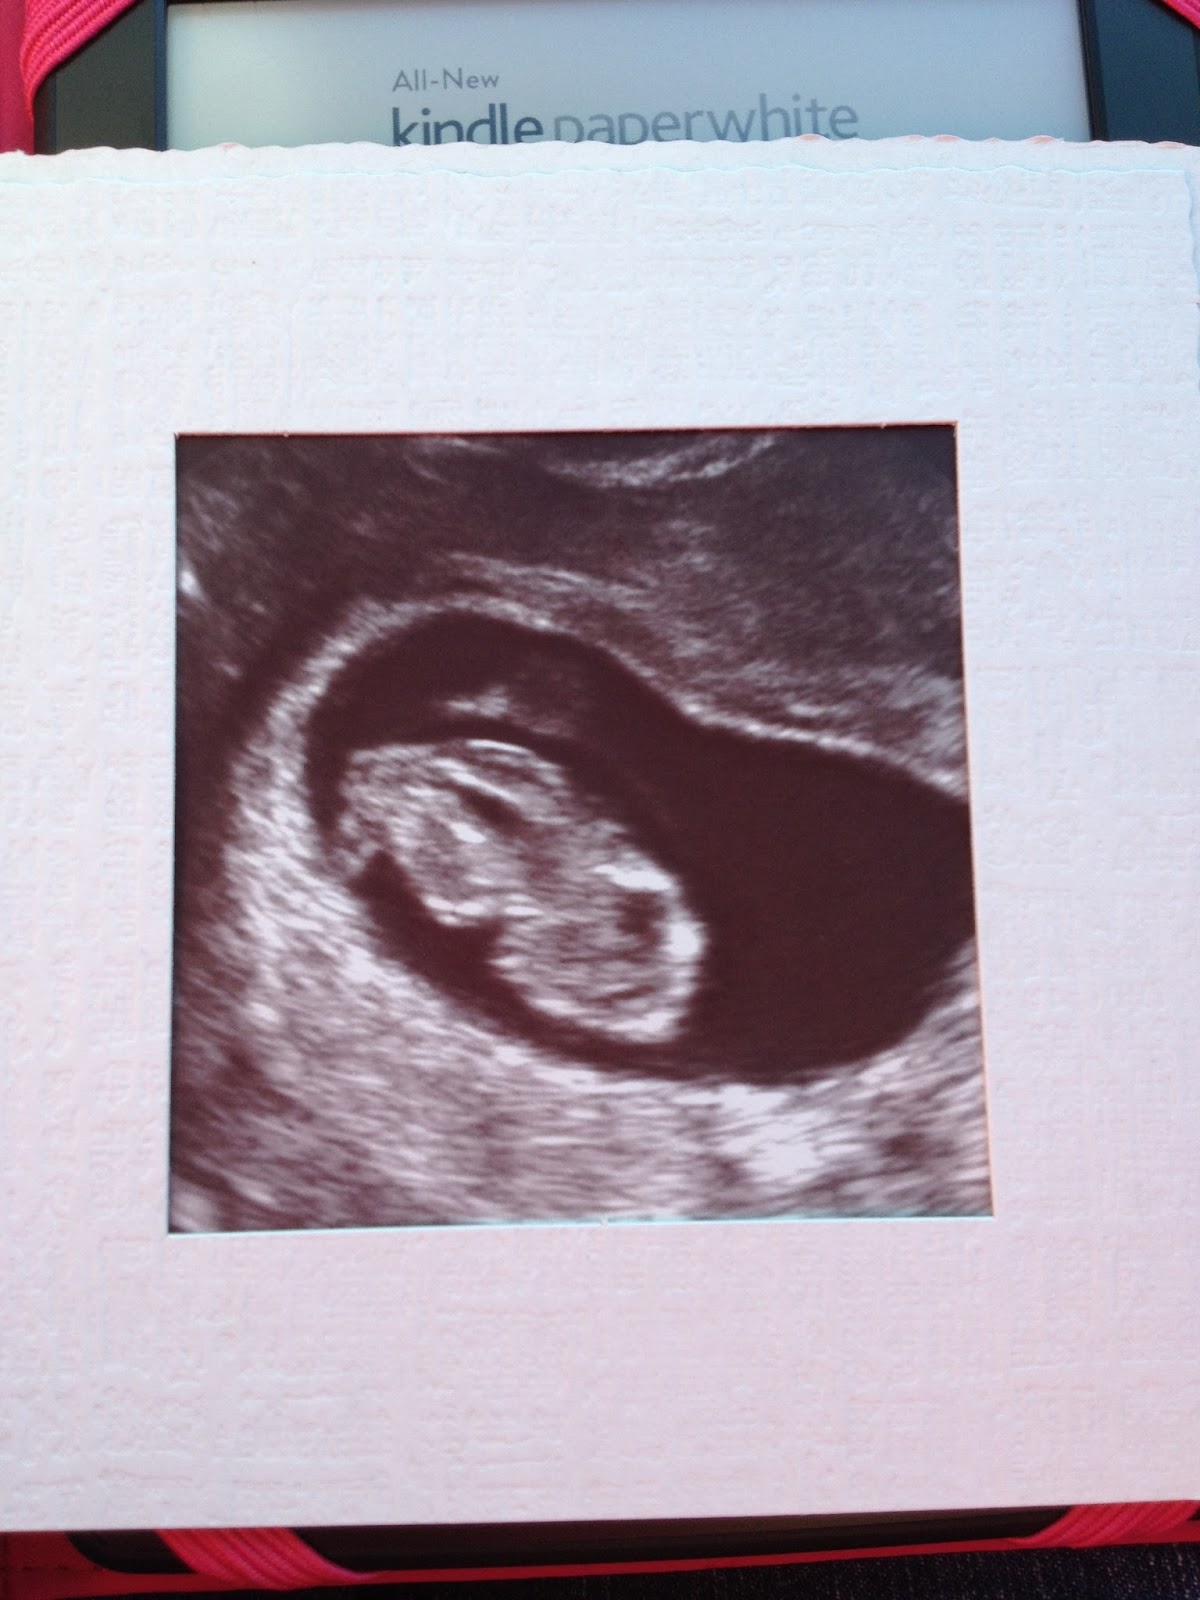

Ultrasound #2 8 weeks 3 days...

The Little Minion is growing fast and furious!! Heart rate today was 171 and doctor said we're measuring right on target for a EDD of 4/27/14! We've officially "graduated" to our OB and will have our first prenatal appointment on October 1st including another ultrasound! We're gonna have an album full of this child before he/she even makes their appearance! I'm still in absolute awe and wonder of this little miracle and can't wait to spend the next 7 months becoming better acquainted! God is so very good!!